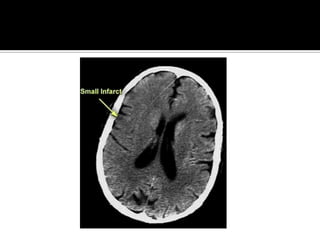

Pregunta 1¿ La lesion    cerebral es causada por una EVC de tipo isquemico o hemorragico o por una entidad no vascular?Respuesta: clinica  y Tomografia computarizada de craneo simple o RM craneal simple

¿Pregunta 2?¿Cual es la localizacion y magnitud de la lesion?Respuesta: TAC o RM

Pregunta 3¿Cuál es la naturaleza ,localizacion, y gravedad de la lesion?Respuesta: clinica y Neuroimagen

Signos tempranos:  TAC en EVC AgudoSigno dela arteria cerebral media hiperdensaAtenuacion del nucleo lenticularHipodensidad cortical o subcorticalEdema cerebralBorrado de la region insularBorrado de surcos corticalesCompresion ventricularAtenuacion de contraste cortico-medular